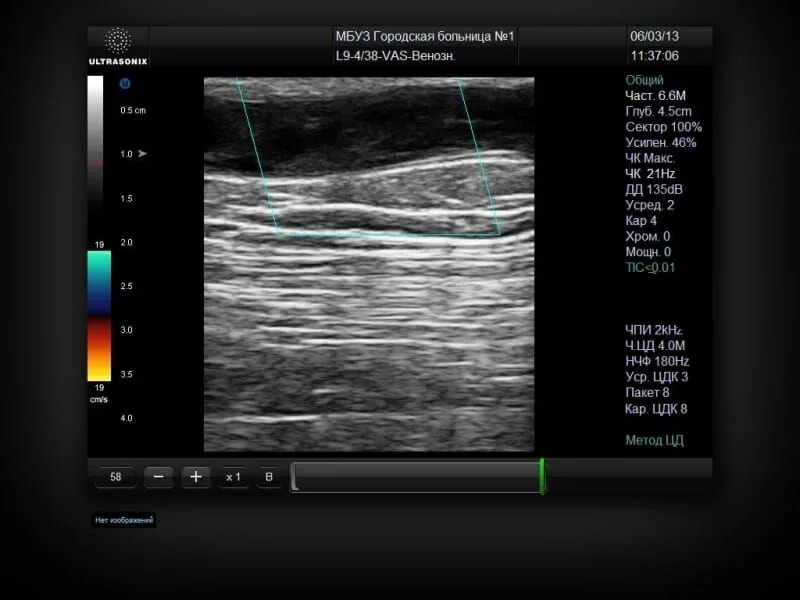

Не лоцируется что это